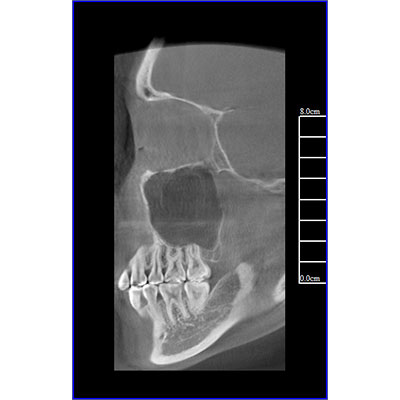

該款牙科CBCT產(chǎn)品采用動(dòng)態(tài)平板探測(cè)器,獲得三維圖像的同時(shí)還具有數(shù)字化全景功能,廣泛應(yīng)用于口腔頜面外科、正畸科、正頜外科、種植科、牙體科、顳下頜關(guān)節(jié)科等術(shù)前術(shù)后。

專有三維重建算法,可提供任意位置高清斷層影像。

可同時(shí)觀察軸向面、冠狀面和矢狀面圖像,方便臨床診斷。